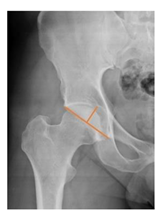

| Acetabular depth/width ratio | The width is a line connecting the superolateral edge and the inferomedial edge of the acetabulum. The perpendicular line from the latter to the deepest part of acetabulum is the depth. The ADWR is the percentage of depth to the width [25] | >38% | ![]() |